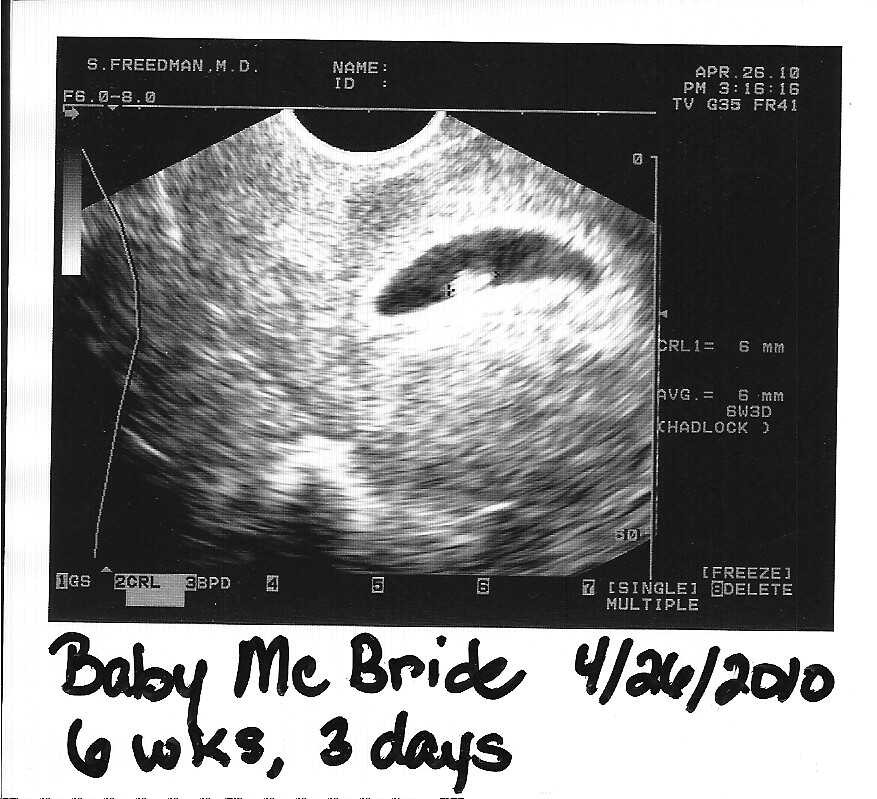

Baby McBride Ultrasound 6 Weeks 3 Days | Nogwater | Flickr

6 weeks and 1 day pregnant – Baby Fetal Progress, Ultrasound, Nutrition …

Baby’s growth at 6 weeks pregnant through ultrasound pictures …

Ultrasound at 6 weeks and 2 days and 7 week belly pics – The Wheelchair …

Vaginal Ultrasound @ 6 weeks. — The Bump